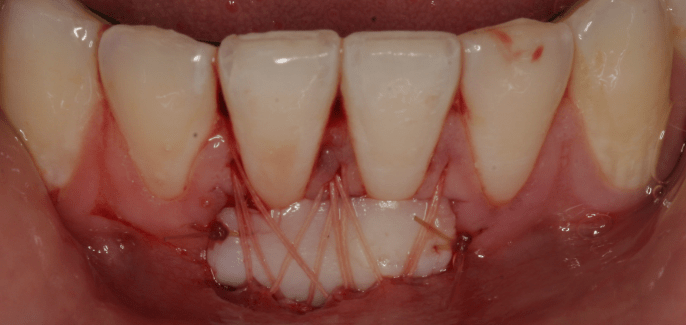

Se a recessão estiver num estádio muito avançado e o paciente tiver sintomas como sensibilidade dentária, dor ou infecção, existem vários tratamentos disponíveis, como, por exemplo, destartarização, antibióticos ou exertos gingivais.

- Cirurgia para colocação de enxerto de gengiva.